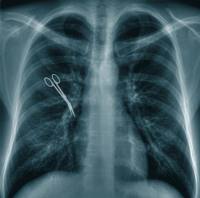

7) Medico che non abbia controllato la completezza e l’esattezza del contenuto

della cartella clinica redatta dai colleghi di pronto soccorso (Cass.

12273/2004);

9) Caso di scuola dottrinale: garza dimenticata nello stomaco del paziente